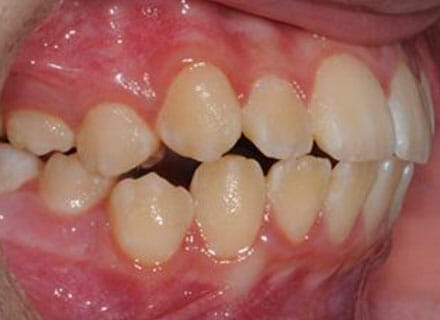

Fixing protruding teeth upper and lower and crowding – no extractions

this patient didn’t like the teeth because they pushed forwards and were sticking out and pushing out her lips. She thought that she looked like she had too many teeth and not enough space. In 12 months we pulled all the teeth back, pulled them together, and lined them all up. No teeth were extracted because we made room by expanding the jaws.